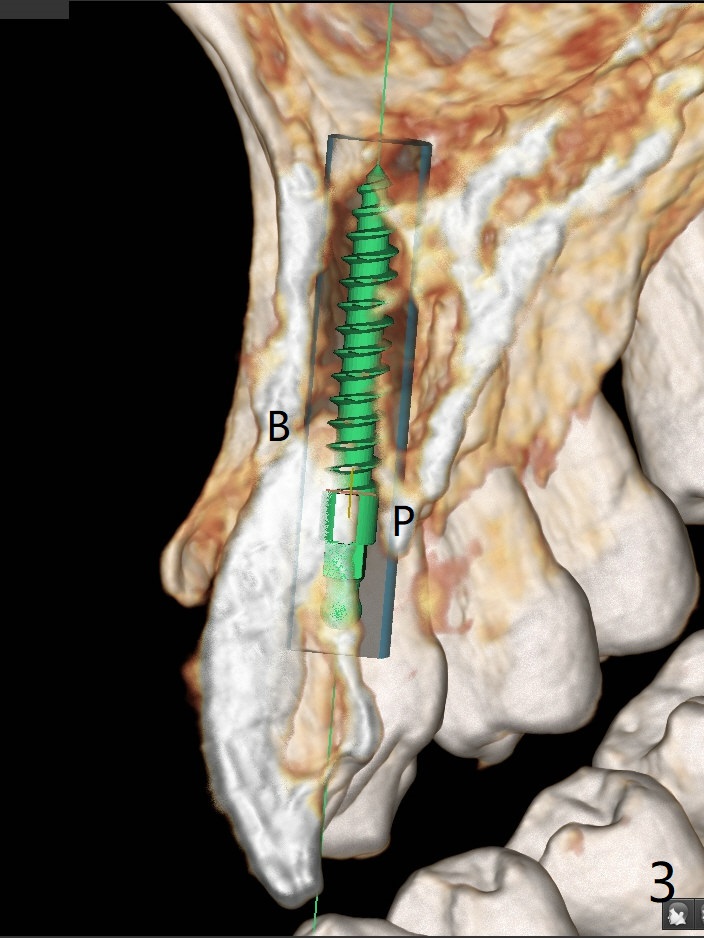

A 58-year-old man recently had sudden pain at #7 with labial plate loss (Fig.1 CT taken 3 years earlier). To avoid the labial placement of the large implants at #8, and 9, the implant at #7 will be smaller and palatally inserted (Fig.2). Fig.3 is a coronal section of 3D image of #7, showing the labial (B) and palatal (P) crests. After extraction (Fig.4 black), the narrow implant is placed between the crests (green). To repair the coronal labial plate, a piece of PRF membrane (Fig.5 blue) is placed inside the socket, followed by sticky bone (red circles). The portion of PRF membrane outside the socket will be flipped palatal, inserted into the abutment with a pre-punched hole and finally tucked underneath the palatal gingiva.